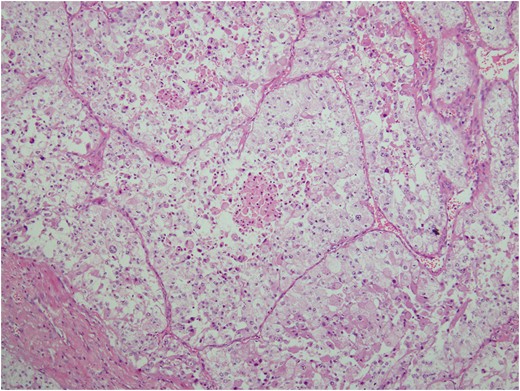

Histologic sections of the mass show distinct variably sized and shaped collections of uniform polygonal tumor cells, separated by fibrovascular septa and delicate capillary-sized vascular channels lined by flattened endothelium at low magnification (Fig. 5). Within the tumor nests, there is loss of cellular cohesion and necrosis of the centrally located cells in the nests results in the pseudo-alveolar pattern (Fig. 6). Vascular invasion is also present (Fig. 7). The individual tumor cells have distinct cell borders and abundant eosinophilic to clear, somewhat granular cytoplasm surrounding a central nucleus with variably sized nucleolus. Nuclear atypia is rarely seen. Mitotic figures are uncommon. The cells contain rhomboid or rod-shaped crystalline inclusions that are faintly apparent on routine histology and are better demonstrated with periodic acid-Schiff stain after diastase digestion (Fig. 8).

Crystalline inclusions demonstrated with periodic acid-Schiff stain after diastase digestion.